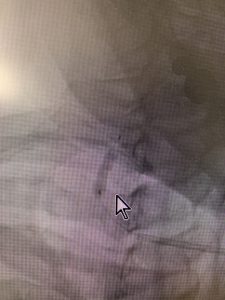

右側の椎骨動脈の起始部の重度狭窄の状況で左鎖骨下動脈の閉塞を認めている複雑な主幹血管の血流不足のある患者様の場合は、まず右側椎骨動脈の起始部の部分を脳血管内手術専門医チームで拡張し、十分な血流を維持した上で左鎖骨動脈の閉塞部分を循環器チームで再開通させる手法をとります。

脳血管内手術治療においては、PTAバルーンを使って拡張し、ほぼ完全に元の太さに修復しました。

その後二週間後に循環器チームで、閉塞している左鎖骨動脈に対し、良好な再開通が得られています。